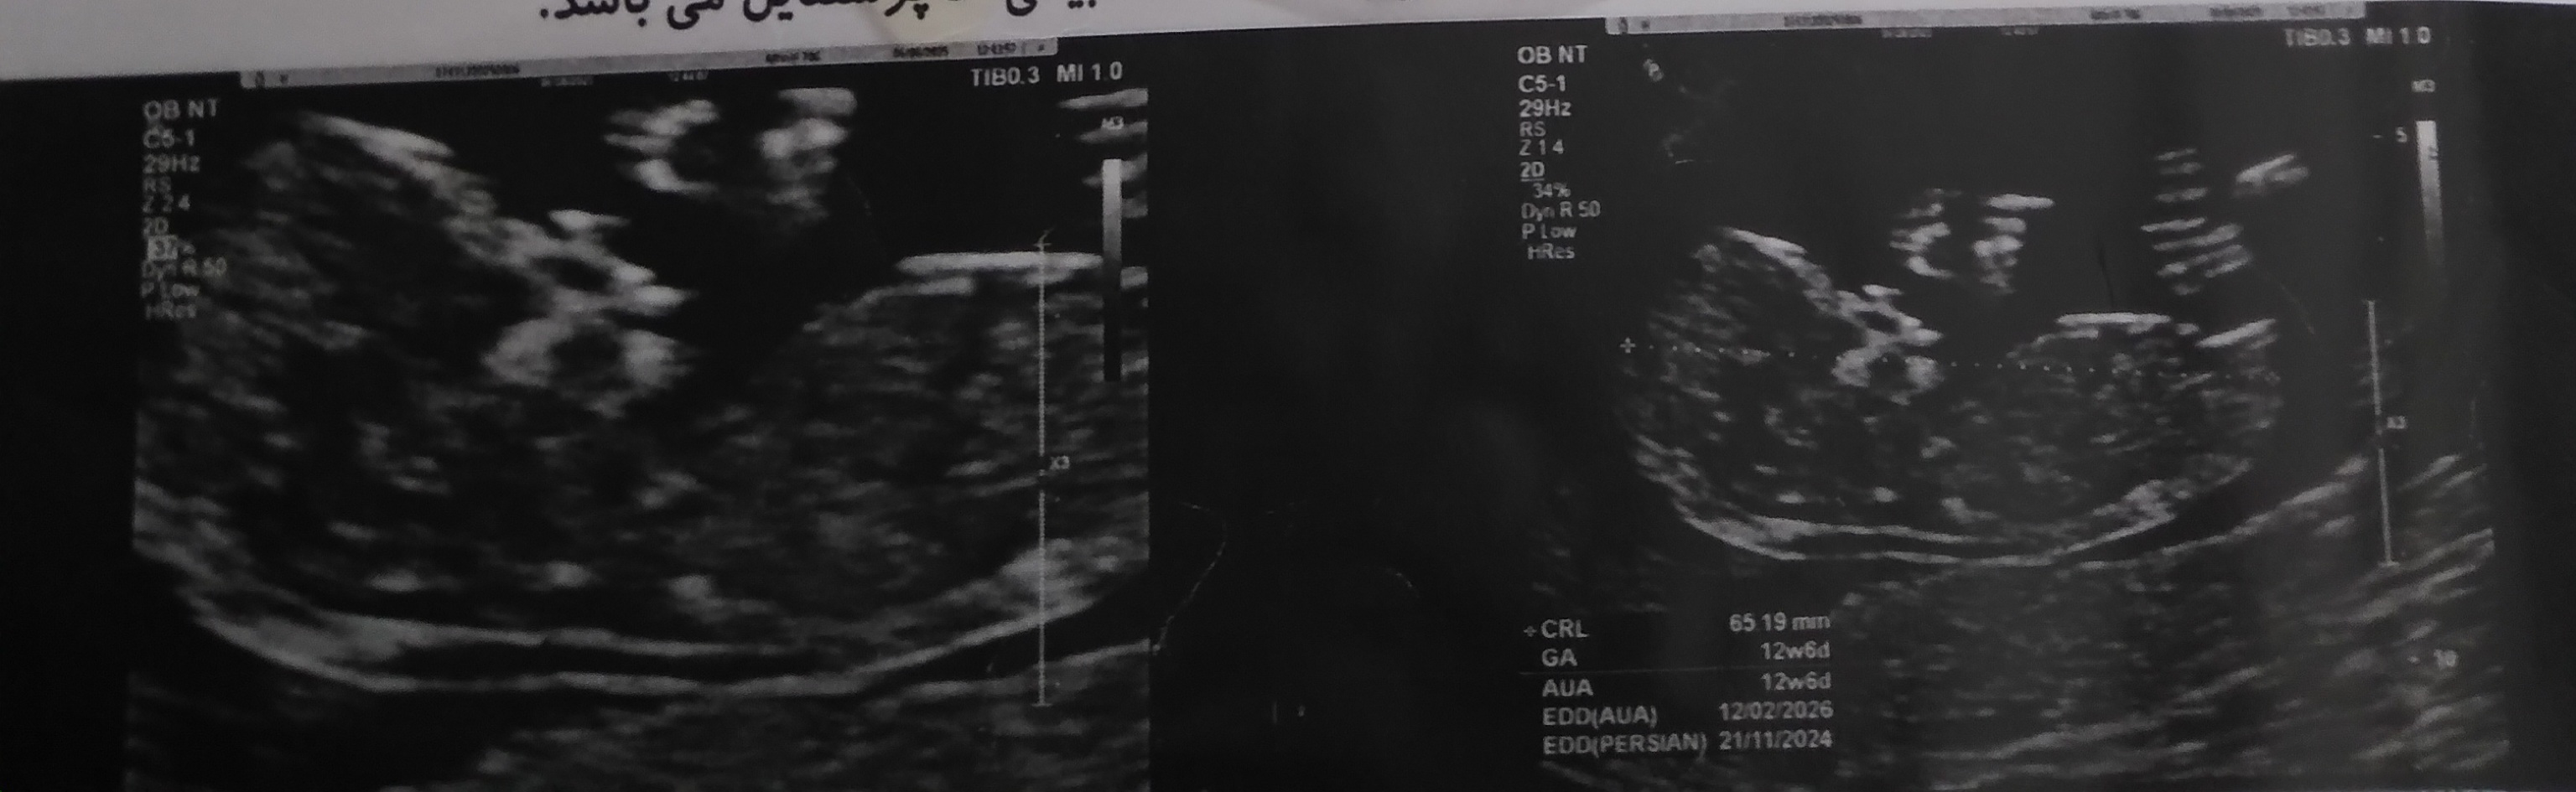

گاوخونی مدیر استارتر عضویت: 1400/10/03 تعداد پست: 74 عنوان سونو ان تی 119 بازدید | 12 پست سلام دوستانی که از رو سونو ان تی جنسیت را تشخیص میدادن لطفا این عکس را ببینید 1404/05/30 | 12:52 0 نفر لایک کرده اند ... گزارش تاپیک نامناسب

گاوخونی مدیر استارتر عضویت: 1400/10/03 تعداد پست: 74 تو قسمتی که تایپ میکنی یه عکس گالری هست ازاونجا عکسا فرستادم

goliiiiiiiiisa عضویت: 1401/08/28 تعداد پست: 15949 نظری نداشتید هیچ کدوم؟ بنظر پسر میاد باز هرچی دکتر سونوگرافیت گفته اون دقیق تره